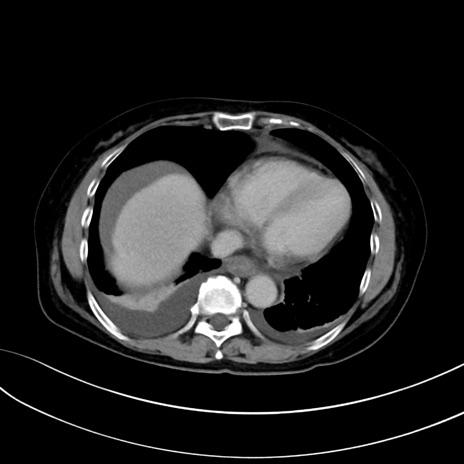

症例13 CT(横断像)1日半後